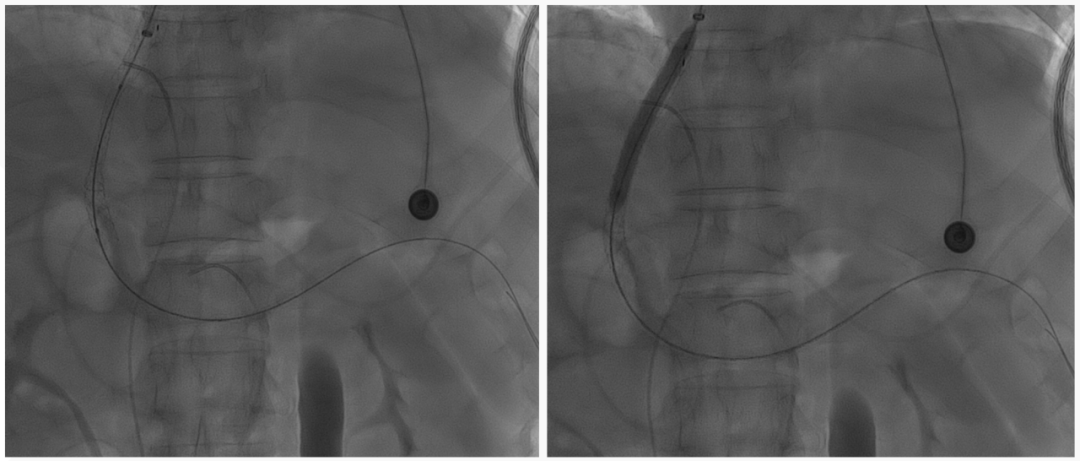

至腸系膜上動脈行間接門靜脈造影,未見門靜脈顯影,可見巨大異常分流道,遂至脾動脈行間接門脈造影可見門靜脈異常纖細,腸系膜下靜脈見異常分流道形成

以微導管行肝動脈標記輔助穿刺,門靜脈造影顯示血流呈離肝狀態(tài)

超選至腸系膜下靜脈異常分流道,予以栓塞18mm的Amplatzer vascular plug及適量25%生物膠,造影示異常分流道消失

8mm覆膜支架釋放于肝內(nèi)穿刺道,考慮門脈纖細,遂以6mm球囊后擴張